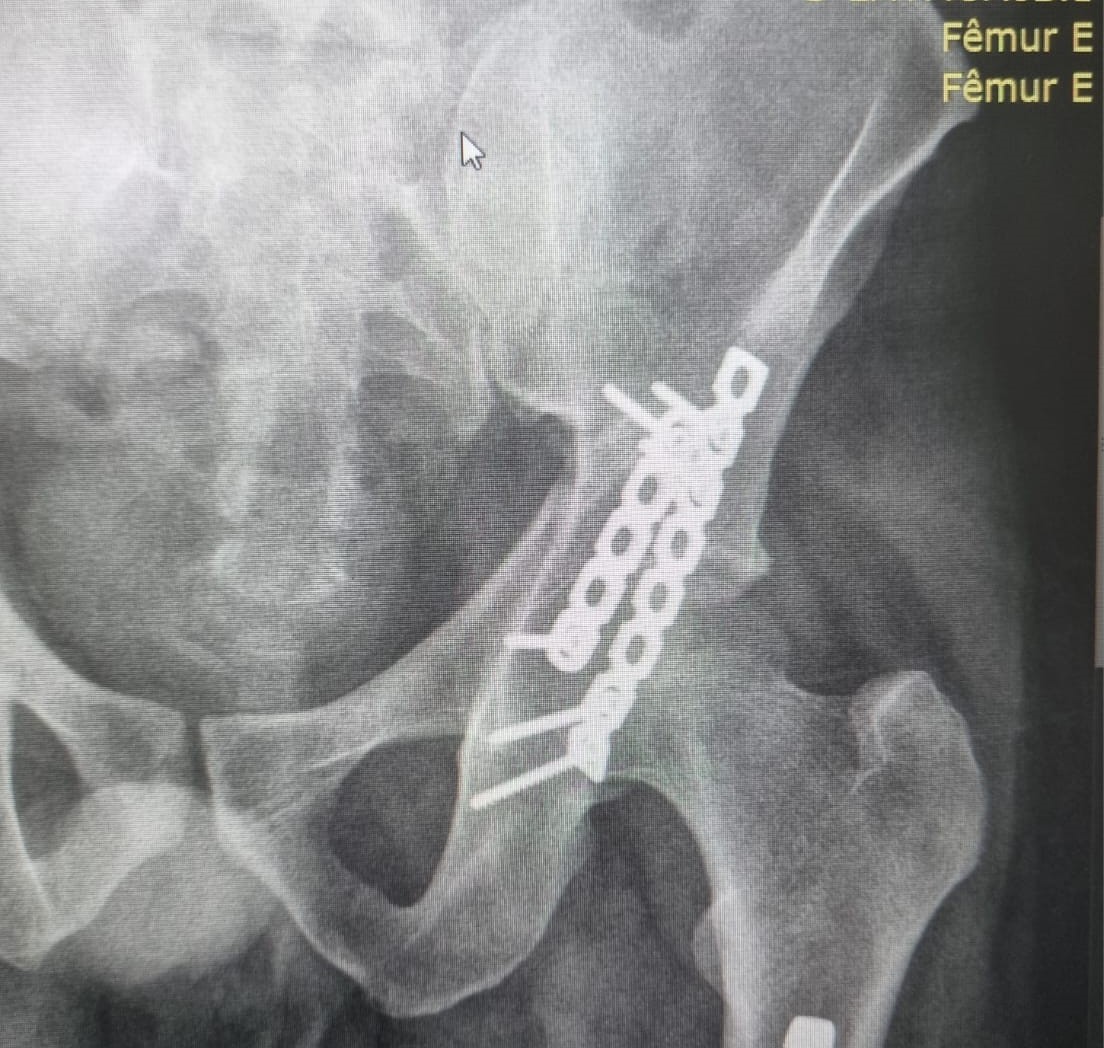

• Fraturas do Anel Pélvico;

• Próteses de Quadril (Primárias  e Revisões);

• Cirurgia do Quadril;